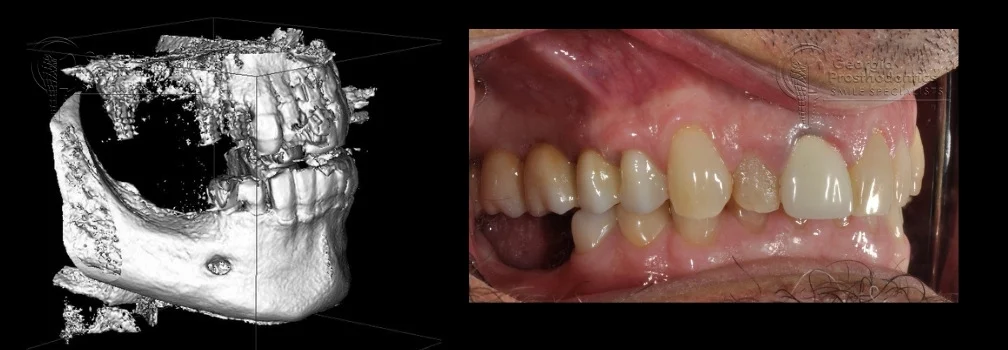

- Thanks to advancements in 3D imaging, CBCT scans, and guided implantology, the placement of pterygoid implants has become more precise, predictable, and safer, making them an increasingly popular solution for dentists and oral surgeons dealing with challenging upper jaw cases.

- Preoperative Planning: Advanced imaging techniques like CBCT (cone beam computed tomography) and 3D scans are essential to assess the patient’s anatomy and the available bone volume for the implant.

- Preoperative Imaging: Cone Beam Computed Tomography (CBCT) and other advanced imaging techniques help the surgeon visualize the anatomy of the maxilla, sinuses, and surrounding structures. These scans provide crucial details about the bone density, volume, and potential obstacles in the implant path.

- CBCT Scanning and Bone Mapping: Before undergoing surgery, a Cone Beam CT (CBCT) scan is essential to map the bone and assess its quality and quantity. This imaging allows the surgeon to determine the best implant position and angle for optimal success.

- Detailed Imaging: A Cone Beam CT (CBCT) scan is performed to assess the bone structure and map out the pterygoid region. The scan helps the surgeon determine if there is enough bone in the pterygoid plate for successful implant placement. It also allows the surgeon to plan the angle and position of the implants.